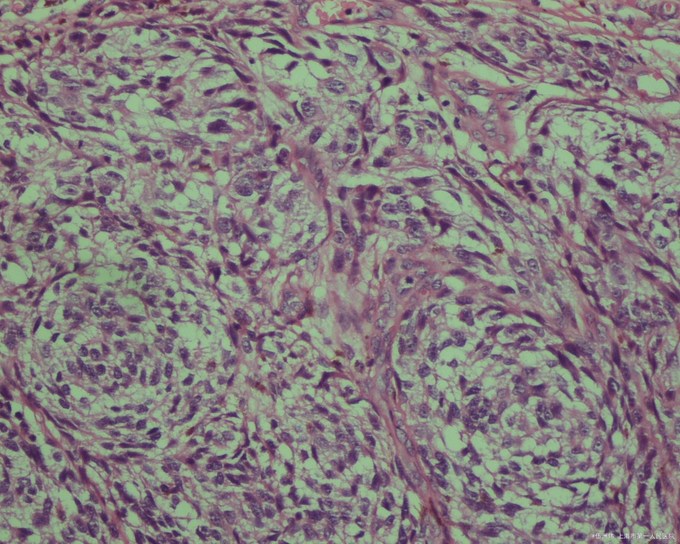

1.组织病理检查 可见黑素细胞异常增生,表皮内或表皮-真皮界处有细胞巢,核仁通常呈嗜酸性的“鸟眼样”,在侵袭性黑瘤,可在真皮或皮下组织内见到黑瘤细胞。 对于典型的黑瘤,一般HE染色切片病理学检查,即可明确诊断,但非典型的黑瘤,如无色素性黑瘤等,常需辅加一些特殊技术(如S-100和HMB-45免疫组化检查)才有助于诊断。 (1)恶性雀斑痣:组织病理早期病变仅见表皮变薄或不变,基底层色素加深,但有些区域的色素可扩展到表皮的较上层,甚至达到角质层,基底层中黑色素细胞密度增高,排列不规则,真皮上层可有少许噬黑素细胞及轻度炎症浸润,比较成熟的损害中,则可见变平的表皮内基底层中黑色素细胞密度明显增高,很多黑素细胞沿表皮真皮交界处任意排列,细胞细长呈梭形,核呈显着异性性,有的皱缩,有的远较正常者大,真皮上部除结缔组织日光变性外,常有明显带状炎症浸润,浸润范围可达周围正常表皮的下方,其中含大量噬黑素细胞。 (2)浅表扩散性原位黑色素瘤:组织病理表皮棘层肥厚,在整个表皮内杂乱散布有相当一致而圆的黑素细胞,瘤细胞主要位于表皮下部,聚集成巢,似paget细胞,而表皮上部的瘤细胞则单个散布,其核不典型,染色深,胞质丰富,含有多少不等的黑素颗粒,几乎都无树枝状突,真皮内有噬黑素细胞与炎症细胞浸润,其浸润范围可超过病变而达到周围正常表皮下方。 (3)肢端雀斑样原位黑色素瘤:组织病理早期损害表皮棘层肥厚,基底层黑素细胞及黑素增多,只有灶性黑素细胞不典型,故易认为是良性病变,以后,瘤细胞偶呈梭形并出现于表皮上部,但多数病例可同时见梭形与圆形Paget细胞,且有时以后者占优势,黑素明显增多,以致在真皮浅层出现噬黑素细胞,并在角质层也可见有大块黑素颗粒聚集。 (4)恶性雀斑样痣性黑素瘤:组织病理早期仍具有恶性雀斑样痣的特点,在深色皮损处取材时可见表皮基底细胞黑色素增多,整个基底层中可见奇形怪状的梭形黑色素细胞,其核有显着的异型性,在淡色皮损处取材时,基底层中可见多数大而异形的黑素细胞,严重者这些异形细胞几乎全部代替了基底层细胞,有些瘤细胞聚集成簇,并已侵袭至真皮,真皮中的瘤细胞呈梭形,聚集成团,含黑色素量不多,而周围的巨噬细胞中则含有很多黑色素,瘤细胞常侵犯毛囊的外根鞘,具有诊断价值,真皮浅层胶原纤维常有嗜碱性变,在肿瘤周围可见带状炎症浸润。 (5)浅表扩散性黑色素瘤:组织病理在侵袭性生长不明显时仍可见Paget细胞样黑色素细胞散布于表皮内,但在真皮乳头内亦见有上述细胞,表示已突破原位,侵袭性生长时,真皮内即出现瘤细胞结节,瘤细胞呈上皮细胞型,梭形细胞型,痣细胞样或混合存在,如以上皮细胞为主,可形成腺泡状结构,周围有细的胶原纤维环绕,在肿瘤病变的临近真皮内可见带状炎症浸润。 (6)肢端雀斑痣性黑色素瘤:组织病理早期损害的主要特点是不典型黑色素细胞以恶性雀斑样痣性黑色素瘤的扩散方式向上移行,但其下方真皮内的胶原纤维无光线性改变,大多数不典型性黑色素瘤细胞聚集在基底层及其上方,但一些小的区域内出现类似浅表扩散性黑色素瘤的改变,以后则向真皮内侵袭性生长,转移快。 (7)结节性黑色素瘤:组织病理瘤细胞侵犯真皮,并出现瘤细胞结节,但邻近表皮内无病变,间或在肿瘤旁可见少许表皮内病变,但一般不超过3个表皮突范围。 (8)痣细胞恶变:组织病理黑痣的恶变通常最早发生在真皮表皮交界处,痣细胞呈异常增生,且痣细胞巢扩大互相融合,在痣细胞巢之间常有异型黑色素细胞增生,异型黑色素细胞不仅在表皮内扩展,而且向真皮内侵袭性生长,在真皮内不出现成熟现象,常有核丝分裂象,偶然,痣细胞的恶变也可从真皮深部开始,但在其他部位仍可见残余的痣细胞。 (9)无色素型恶性黑色素瘤(amelanotic malignan melanoma)组织病理:在HE染色切片中无明显黑色素可见,但多做切片或银染,仍能发现少数细胞含有黑色素,如用电镜检查或以新鲜组织作dopa反应则能证实黑素的存在,故无黑色素性恶性黑色素瘤并非没有黑色素,只是在常规染色中不能见到而已。

诊断要点 临床表现 皮肤恶性黑素瘤可分为四种类型,即恶性雀斑样痣(一种原位黑素瘤)、表浅性播散性黑素瘤、结节性黑素瘤和肢端雀斑样痣黑素瘤。这四种类型的黑素瘤各有特点,它们共同的特点为好发于40岁以上的中老年人,好发于日光照晒部位或摩擦挤压部位,损害为带有黑素的肉瘤样肿瘤,发展快速,容易破溃,经常出血,肿瘤的基底部总会有黑色,很快近卫淋巴结转移,迅速转移到重要脏器导致死亡。 诊断标准 本病为肉瘤样肿瘤,基底部有黑色浸润,极易出血,发展快速,容易转移。组织病理为黑素细胞的恶性肿瘤,根据病理侵犯的深度可分为五级。Ⅰ级:恶性黑素瘤细胞限于表皮。Ⅱ级:侵及真皮乳头层。Ⅲ级:侵及乳头下血管丛,但尚未侵入真皮网状层。 鉴别诊断 本病应与色素性基底细胞癌、色素痣、蓝痣、鳞状细胞癌及良性幼年黑素瘤等病相鉴别。 治疗概述 手术切除 越早越好,切除的范围要根据黑素瘤的深度来确定。Ho等介绍,黑素瘤肿瘤<1.0mm,切除周边范围1cm;深度为1.0~1.5mm,切除周边范围1.5cm;深度为1.5~4.0mm或>4mm,切除范围为3cm。而深度要达肌筋膜。如果是肢端黑素瘤,需要考虑截肢术。 选择性区域淋巴结切除术 因为黑素瘤患者近卫淋巴结的转移度高达90%,因之,黑素瘤的近卫淋巴结要做早期手术切除,足部黑素瘤不仅要切除腘窝淋巴结,还要切除腹股沟淋巴结。 化学灌注疗法 适用于肢体的黑素瘤,用米尔法兰做患肢端动脉注射以灌进黑素瘤体内。这种技术成功,可减少截肢术的应用。 化疗 黑素瘤的晚期或有广泛转移必须采用联合化疗,联合化疗方案有,白介素2+顺铂+长春新碱+达卡巴嗪;BELD,即博莱霉素加癌的散加环己亚硝脲加氨烯咪胺等联合化疗方案。Kessinger等对105例用大剂量化疗和自身骨髓移植,48%缓解,34%好转。 免疫疗法 免疫疗法治疗黑素瘤还在研究中,用非特异性免疫刺激剂卡介苗(BCG)注射到黑素瘤的瘤体中有的病例有疗效,总的估计大约有58%注射结节和14%未注射结节好转。 生物反应修饰剂:采用重组干扰素治疗黑素瘤有些进展。用中到大剂量干扰素治疗309例,平均为15%的有效率。也有用重组白组胞介素:治疗播散性黑素瘤,早期报道对内脏和皮肤转移肿瘤的缓解率最高为50%。 放射治疗 原来黑素瘤对放射治疗是抵抗的,现在使用大剂量(每阶段>4Gy),其治愈率。最低从0~25%,最高从45%~71%。近来证明用人工加热器可以增加放射线的疗效。在放射治疗前或治疗中温度升高到42℃或43℃达30~45min,可以提高疗效。 其他治疗 (1)壬二酸(azelaic acid):用20%壬二酸霜治疗50例黑素瘤,所有病例都获临床和组织学吸收。 (2)维A酸类:Levine等报道2例皮肤转移黑素瘤局部外用维A酸,1例临床和组织学缓解,另1例有部分临床和组织学缓解。